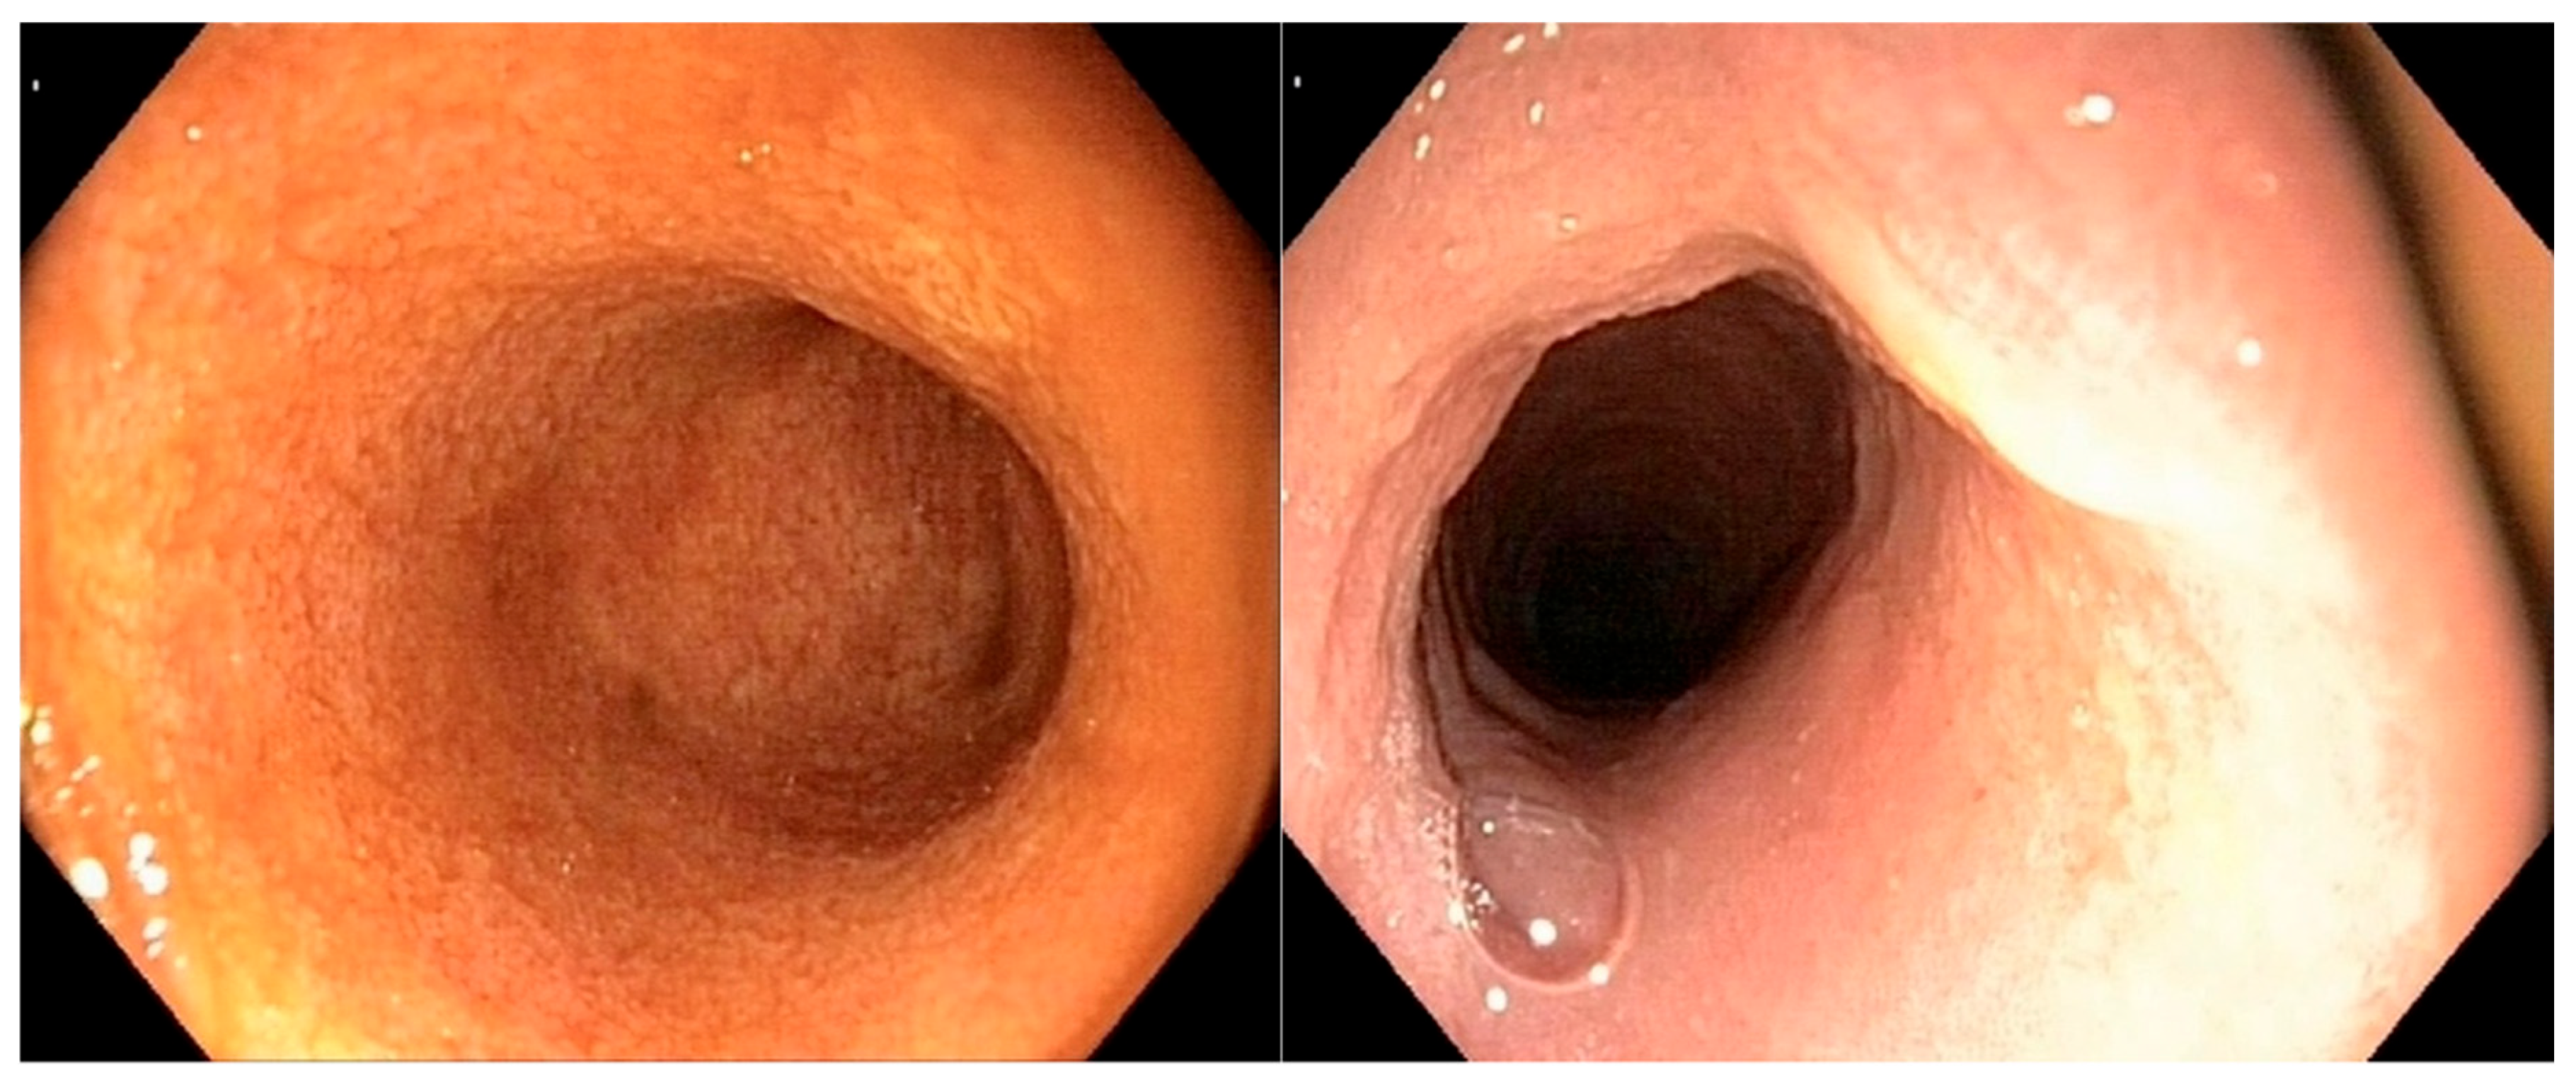

All of the endoscopic findings are summarized in Table 3. Figure 2 illustrates a severe alteration in the granularity of the duodenal mucosa during duodenoscopy. Duodenal lacteal dilatation was observed in one dog (6%). A “cobblestone” appearance of the duodenal mucosa was identified in nine dogs (53%) (Figure 3). No dog developed colonic stricture or intussusception.

Figure 2. Duodenoscopy of dog n°9 (confirmed large-T-cell duodenal lymphoma): very severe alteration in the granularity of the duodenal mucosa.